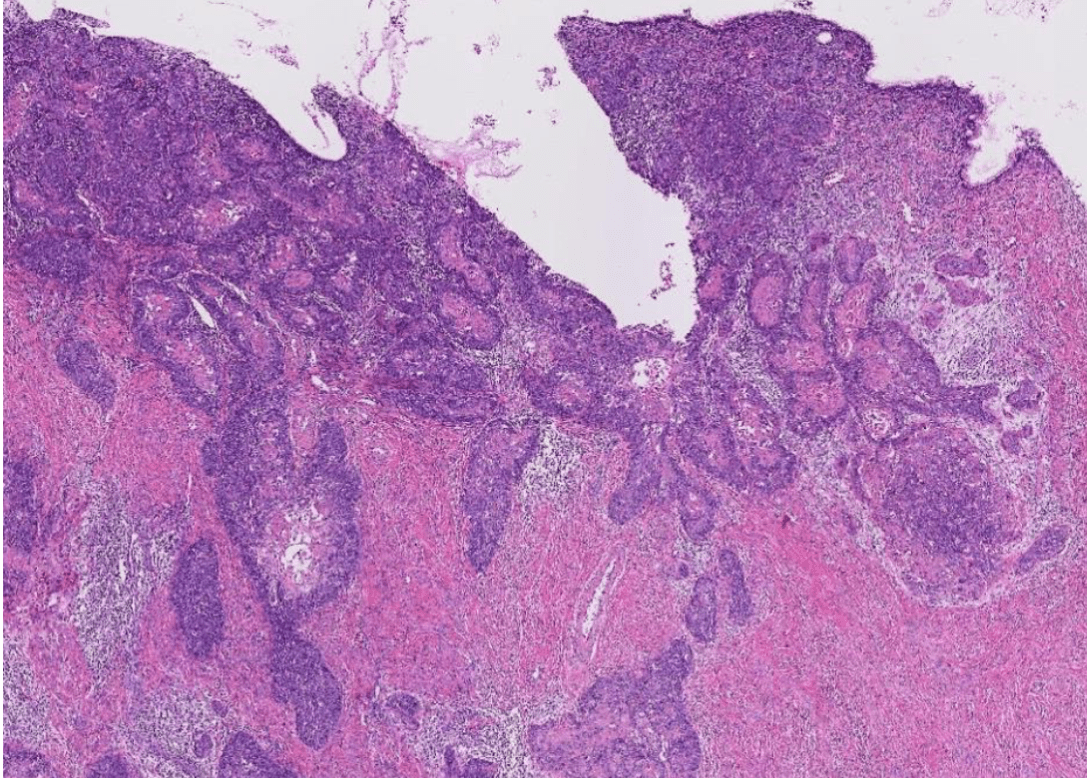

colon cancer